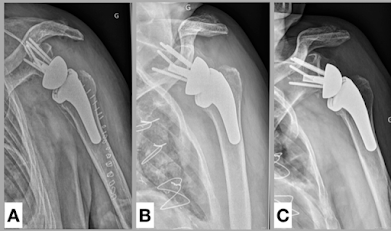

Lack of a good fit in the variable humeral canal can result in high rates of loosening of short stemmed humeral components as demonstrated in Radiographic evaluation of short-stem press-fit total shoulder arthroplasty: short-term follow-up. Symptomatic aseptic loosening of a short humeral stem following anatomic total shoulder arthroplasty assessed 184 shoulders that received TSA with a grit-blasted, rectangular short humeral stem without ingrowth coating. The rate of symptomatic aseptic humeral loosening in this series was 10.9%, with 5.4% undergoing revision surgery. Note the components below have subsided into varus with lateral diaphysial erosion.

Subsidence of Uncemented Short Stems in Reverse Shoulder Arthroplasty-A Multicenter Study reviewed 139 patients at a minimum follow-up of 12 months. The average subsidence was 1.4 mm. Subsidence of >5 mm was present in 15 patients (11%). Note once more that the component has subsided into varus with lateral diaphysial erosion.

It appears that without the stabilizing effect of a standard length stem, loading of a short stemmed component can cause it to collapse into varus.